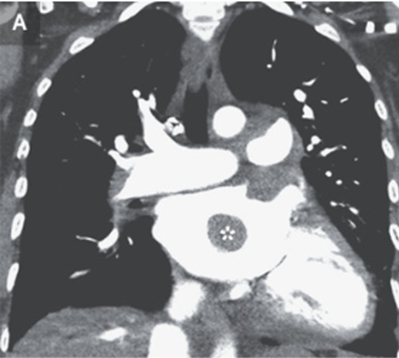

ECGでは動性頻脈が示され、造影CTでは肺幹および左右の主肺動脈に血栓が見られた。また左心房には境界明瞭な造影欠損領域が認められた。